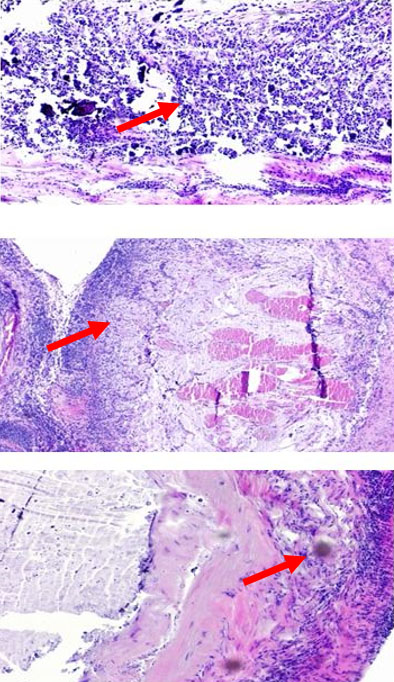

Contrast-enhanced abdominal CT and MRI scans revealed significant thickening and dilation of the appendix (Figure 1 and Figure 2). Post-contrast imaging demonstrated slight enhancement of the appendiceal wall. Pathological analysis confirmed the presence of LAMN (Figure 3). Laparoscopic surgery was performed, revealing a markedly dilated appendix (Figure 4). A linear cutter/stapler was used to perform a laparoscopic ileocecal resection. The resected appendix measured 15 cm in length and 4 cm in width. Postoperative pathology confirmed tumor invasion throughout the appendix, with mucin accumulation observed in the apical portion and within the subserosal (SS) layer. The resection margins were negative for tumor involvement. The patient received symptomatic and supportive care, including nutritional therapy, without the need for antibiotic therapy. She was discharged on postoperative day 4 without complications such as abdominal bleeding, intestinal obstruction, or incision infection. During an outpatient follow-up in December 2024, routine blood tests, biochemical analyses, tumor marker assessments, and chest and abdominal CT scans revealed no evidence of recurrence.

Figure 3: Histopathological analysis confirming LAMN.

Share Image: